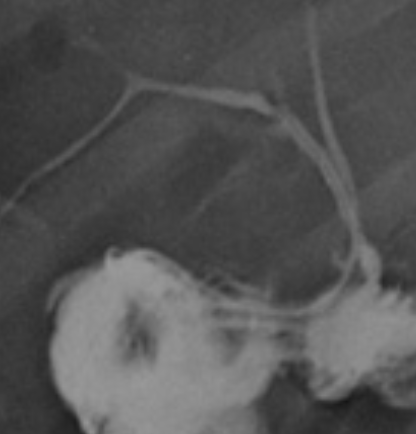

Imágenes y Cirugía

Diego Soto V, Cristian Marín O, Sebastián Morales Z